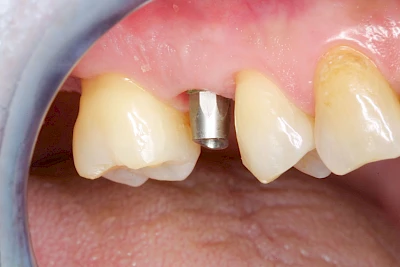

Implantate sind künstliche Zahnwurzeln. Nach einer gewissen Einheilzeit im Knochen (meist 3-6 Monate) erfolgt über einen separaten Aufbau (Abutment) die Befestigung einer Krone bzw. Brücke oder Zahnprothese.

Fehlen einzelne Zähne und die Nachbarzähne sind unbeschadet oder gut zahnärztlich versorgt, werden immer häufiger Implantate gewählt, um die Lücken zu schließen. Auch bei größeren oder verteilten Lücken, wenn keine herausnehmbare Prothese gewünscht ist, werden Implantate für Kronen- bzw. Brückenversorgungen gesetzt. In Einzelfällen entscheiden sich sogar zahnlose Patienten für eine festsitzende Versorgung auf Implantaten.